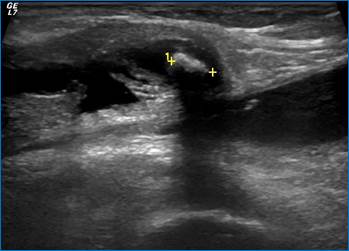

Рис. 1. Выпот в полости сустава, утолщение синовиальной оболочки

Зачастую может быть обнаружен выпот в полости того или иного сустава (рис. 1).